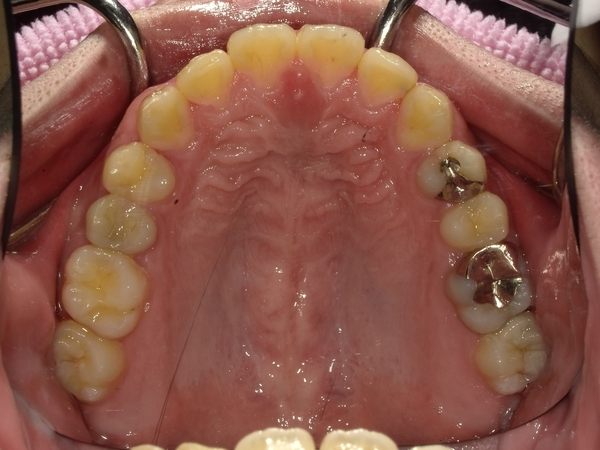

すきっぱ(空隙歯列)CASE7 2023.08.28 20代男性☆Before→After☆〇ご相談内容:前歯真ん中の隙間があいている〇矯正の種類:マウスピース型矯正「インビザラインGO」〇治療期間:19週間〇治療費用:44万円(税込) < すきっぱ(空隙歯列)CASE8すきっぱ(空隙歯列)CASE6 > ブログ記事一覧をみる